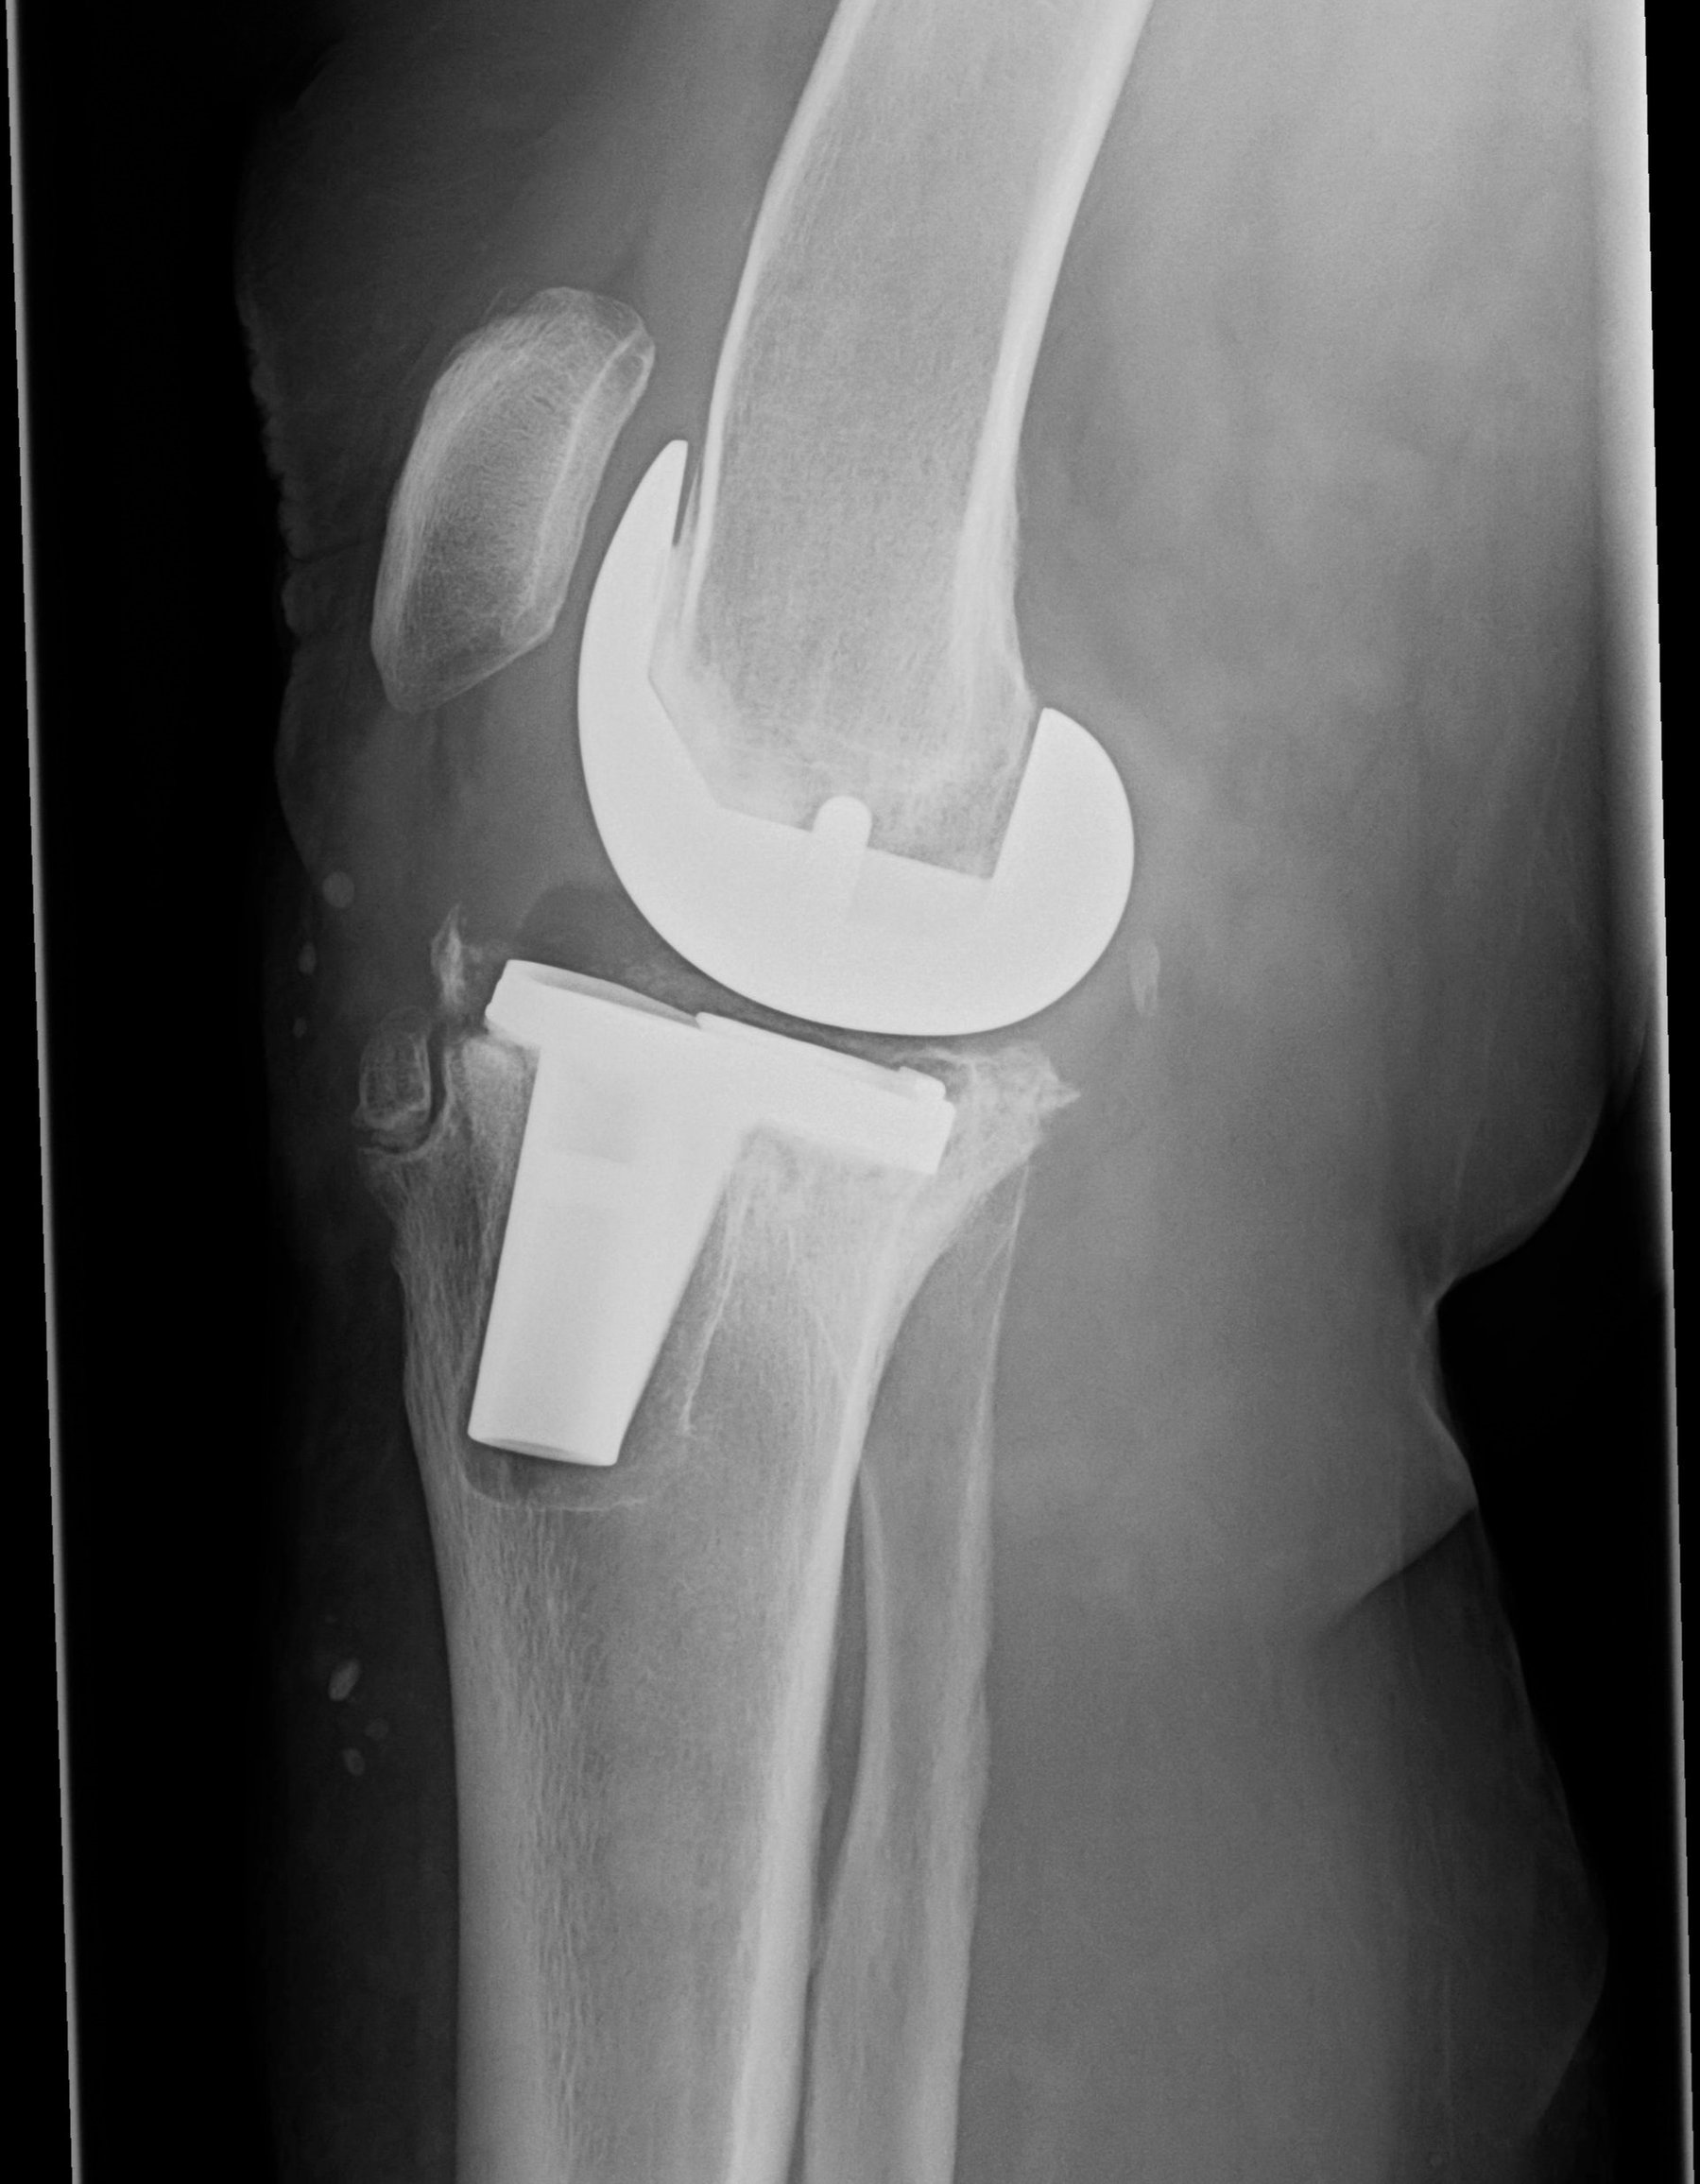

REVISION REPLACEMENT SURGERY FROM A TOP KNEE SPECIALIST

Revision Knee Replacement

When a joint replacement no longer functions as it should, revision surgery can restore mobility and relieve pain. Over time, implants may wear out, loosen, or fail due to issues like infection, dislocation, or mechanical breakdown. If you're experiencing pain, swelling, or joint instability after a previous replacement, it may be time to explore your options.

Revision replacement surgery is performed when a previous joint implant fails to function correctly. This could be due to implant loosening, wear over time, dislocation, fracture around the implant, or joint infection. These issues can cause pain, stiffness, swelling, or instability, and often limit daily activities. Some patients may also experience an audible clicking or sensation of the joint "giving out." When these symptoms emerge, revision surgery may be necessary to restore mobility and quality of life.

In each case, Dr. Haben conducts a comprehensive evaluation including physical exams, imaging, and a review of your implant history. Once he determines the cause of failure, he will develop a customized surgical plan to remove the failed components and replace them. Some revisions are partial, while others may require full reconstruction of the joint and surrounding bone.

While a standard knee replacement involves replacing a worn-out or arthritic joint for the first time, revision surgery addresses complications or failures of a previous implant. Revision procedures may involve replacing one or all parts of the implant, managing infection, or reinforcing areas of bone loss.